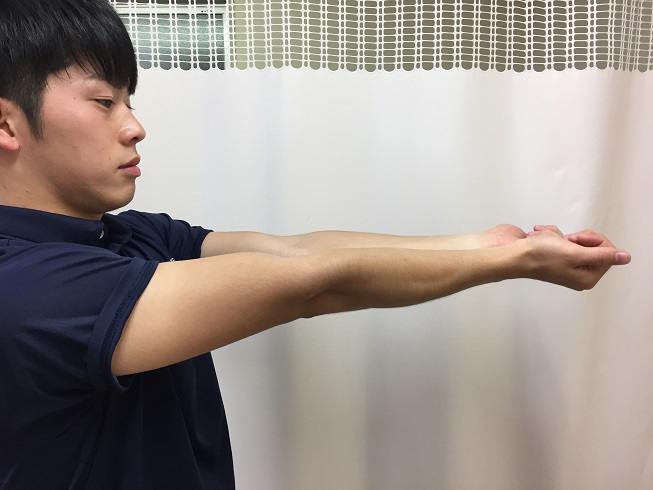

팔꿈치에 문제가 있으면 동작 범위가 제한 될 수 있습니다. 확장 및 굴곡 움직임을 확인하십시오. 또한 손목 굴근의 견인 스트레스는 내측 통증을 유발하고 신근의 견인 스트레스는 측면 통증을 유발합니다. 또한 손목 굴곡 (발바닥 굴곡) 및 손목 확장 (배측 굴곡)에서 제한된 동작 범위를 확인합니다. 동작 범위는 약 90 도입니다.

사진 8 팔꿈치 확장 : 가슴 앞에서 팔꿈치를 확장합니다. 왼쪽과 오른쪽을 비교하면서 뻗치는 제한을 확인하십시오.

사진 10 손목 확장 : 왼쪽과 오른쪽을 비교하면서 확장 제한 및 스트레칭 통증을 확인합니다.